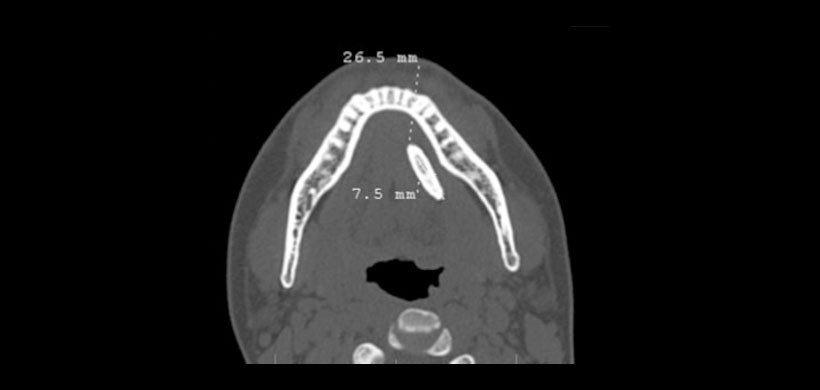

2 meses. Se realizó una TC, la cual mostro mostró un cálculo en el conducto submandibular izquierdo de 28,5 mm (Fig. 1).Luego de la escisión del cálculo el tamaño real del espécimen postoperatorio del cálculo resultó ser de 33,3 9 10 mm (Figuras 2 y Figura 3).